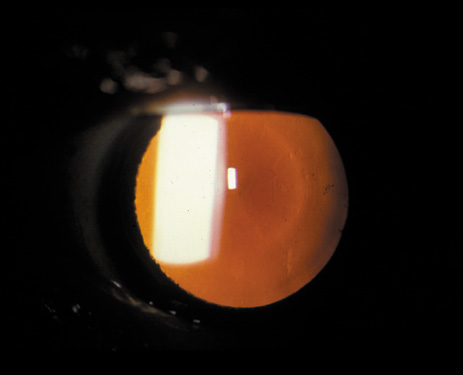

It has been observed that some individuals may have cortical opacities covering the entire anterior cortical and posterior cortical area (Fig. 11), and yet have 20/40 or better Snellen visual acuity under standard testing conditions. However, these patients may have severe disability glare such that under simulated bright lights their visual acuity may decrease to 20/80 or worse.31 They may also have decreased contrast sensitivity. These individuals tend to do well indoors but have difficulty driving during bright, sunny days, and at night because of oncoming headlights. Treatment in these cases must be decided on an individual basis, and surgery may be indicated when the expected benefits outweigh the surgical risks.

Fig. 11. Advanced cortical cataract. Although this type of cataract may be compatible with a Snellen visual acuity of 20/40 or better, it may give rise to severe glare disability.